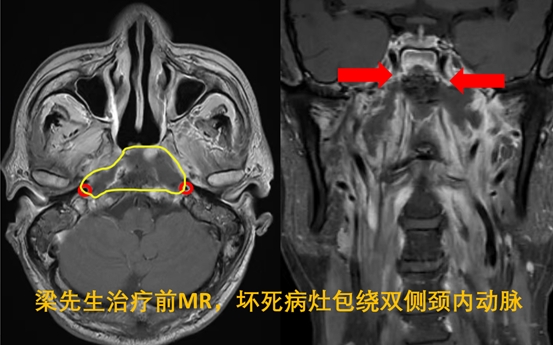

正值壮年的梁先生,实际上是一位与肿瘤抗争了7年之久的老病号,2016年3月在外院诊断鼻咽癌,放化疗治疗2年后在复查中发现肿瘤再次复发,在上海再次行质子重离子放射治疗。去年9月份,梁先生出现了剧烈头痛,于外院诊断“鼻咽坏死”,广泛的病灶侵犯了双侧颈内动脉,此类鼻咽坏死的切除手术,术中颈内动脉破裂风险极高,对于外科医生是一个极大的挑战。

梁先生鼻咽大面积的坏死灶已经包裹双侧的颈内动脉,随时可能发生致命的颈内动脉破裂。所以首先需要行介入手术保护血管,介入栓塞是预防鼻咽坏死颈内动脉大出血的重要手段,但栓塞只适合于一部分侵犯单侧颈内动脉的患者。此患者鼻咽坏死侵犯了双侧颈内动脉,陈教授团队对其进行一侧颈内动脉栓塞,对侧颈内动脉支架置入的方式保护颈内动脉。陈教授团队多年系统性开展侵犯颈内动脉的鼻咽癌放疗后复发和坏死的临床诊疗项目,在处理这一类疾病方面积累了丰富的经验。

梁先生分别在2022年9月、10月在广医五院成功实施了左侧颈内动脉栓塞术和右侧颈内动脉支架置入术,有效预防了颈内动脉破裂出血,为鼻咽坏死手术提供了保障,争取了时间。